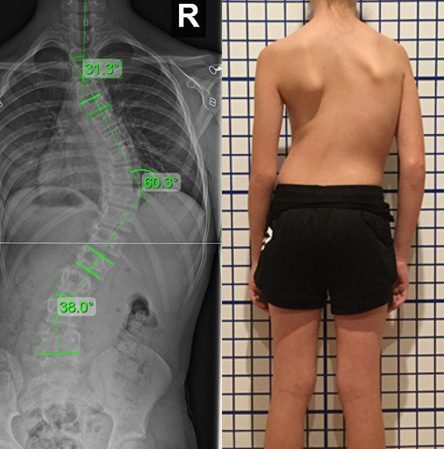

الضغط الصحيح لحزام اعوجاج العمود الفقري: الضلع أم الفقرة؟ عندما يُشخَّص الطفل أو المراهق بوجود اعوجاج في العمود الفقري، يبدأ الأهل في البحث عن أفضل طرق العلاج غير الجراحي. ويعد حزام اعوجاج العمود الفقري

ضغط حزام اعوجاج العمود الفقري : كيف يؤثر على العضلات والعظام والأقراص بين الفقرات؟ يعاني بعض الأطفال والمراهقين من اعوجاج العمود الفقري مجهول السبب عند المراهقين، وهي حالة يحدث فيها انحناء غير طبيعي في

مؤشر جديد يتنبئ بتطور الأنحناء مع حزام اعوجاج العمود الفقري عند المراهقين بسهولة يعاني بعض الأطفال والمراهقين من اعوجاج العمود الفقري مجهول السبب، وهي حالة يحدث فيها انحناء جانبي غير طبيعي في العمود الفقري